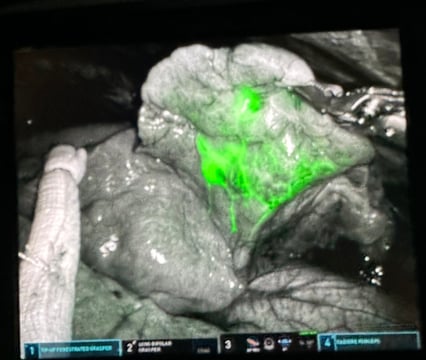

One such technology is Cytalux, a fluorescent imaging agent that binds to cancer cells and glows under near-infrared light, allowing surgeons to more accurately and thoroughly identify and remove tumor tissue.

Cytalux in action.

“When you give Cytalux as an infusion the day before or a few hours before surgery, it preferentially binds to the tumor and lights up the spot in the lungs,” Meguid says. “We use it largely in patients with metastatic cancers to their lung — for instance, colon cancer that has metastasized to the lung — because it helps us pick up spots that are too small to be seen with the naked eye.”

Not every patient is a good candidate for Cytalux, says Elizabeth A. David, MD, MAS, professor of cardiothoracic surgery, but for those with smaller tumors, the technology can be a boon for thoracic surgeons.

“Based on our recommendations for surgically treating lung cancers, when a tumor is less than two centimeters, the appropriate surgical treatment is doing either a segmentectomy — just removing a section of the lung — or a wedge resection, in which a small, triangle-shaped piece of tissue, including the tumor, is removed,” she says. “Those are the cases where we can use Cytalux to enable us to pinpoint where the tumor is and resect a minimal amount of lung tissue. We still do a lymph node dissection for those patients to make sure they're getting the appropriate operation.”